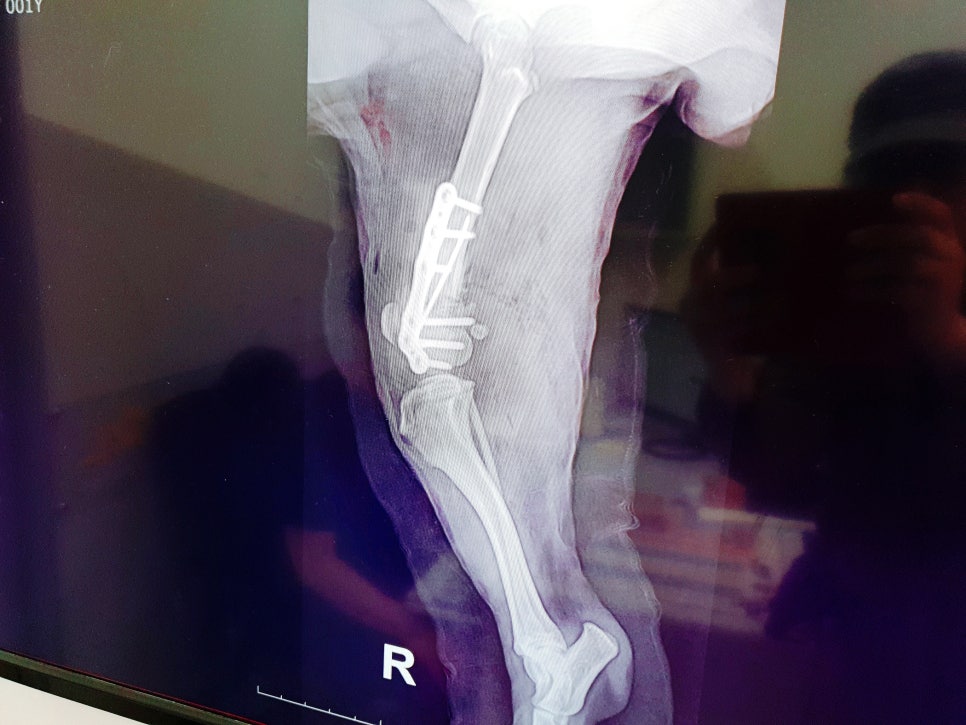

설탕이는 뒷다리에 임플란트로

고정을 해서 평생 임플란트를

심고 살아야 한다고 하더라고요

뒷다리가 어찌나 얇고 말랐던지